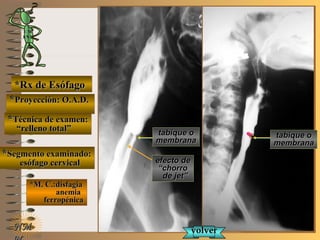

*Rx de Esófago*Rx de Esófago

**Proyección:Proyección:

**Técnica de examen:Técnica de examen:

**Segmento examinado:Segmento examinado:

*M. C.:disfagia*M. C.:disfagia

anemiaanemia

ferropénicaferropénica

NMNM

O.A.D.O.A.D.

““relleno total”relleno total”

esófago cervicalesófago cervical

A-A-El examen es normal o patológico?El examen es normal o patológico?

Examen patológico de esófago cervical, conExamen patológico de esófago cervical, con

relleno total en proyección O.A.D.relleno total en proyección O.A.D.

B-B-La patología es congénita o adquirida?La patología es congénita o adquirida?

Patología congénitaPatología congénita

C-C-Puede describir la o las imágenes patológicas?Puede describir la o las imágenes patológicas?

**OpciónOpción

de volverde volver

a ver lasa ver las

imágenesimágenes

Se identifica una pequeña “indentación” enSe identifica una pequeña “indentación” en

el borde antero-superior del esófago cervicalel borde antero-superior del esófago cervical

inmediatamente por debajo de la unión faringoinmediatamente por debajo de la unión faringo

esofágica o “boca de Killian” a nivel de C6, queesofágica o “boca de Killian” a nivel de C6, que

disminuye el calibre esofágico afectando el flujodisminuye el calibre esofágico afectando el flujo

laminar del contraste y provocando el efecto delaminar del contraste y provocando el efecto de

““chorro de jet” con alteración de la homogenei-chorro de jet” con alteración de la homogenei-

dad de la columna baritada (Síndrome de Plu-dad de la columna baritada (Síndrome de Plu-

mmer-Vinson)mmer-Vinson)

**Opción avanzada para volver a ver las imágenes con reparosOpción avanzada para volver a ver las imágenes con reparos

**Proyección: O.A.D.Proyección: O.A.D.

tabique otabique o

membranamembrana

efecto deefecto de

““chorrochorro

de jet”de jet”

volvervolver